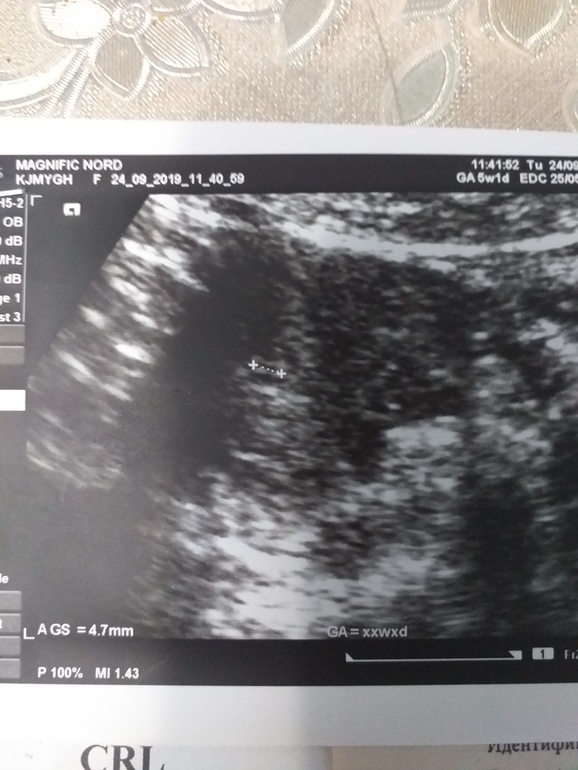

Александра в Копилка тестов // 6 лет У нас получилось! У нас ПОЛУЧИЛОСЬ!!! (Финальный тест, пожелания) Посмотрите еще 20 записей на эту тему Отменить Ответить Настя Поздравляю! Чихните на меня)) пожалуйста) 28.09.2019 Ответить Александра Пусть у вас скоро появятся такие🤞🙏🙏🙏🤧🤧🤧🤧🤧🤧апчхи 29.09.2019 Ответить Светлана Во сколько на УЗИ ходили? Сб есть? Поздравляю вас🤗 Растите здоровенькими 😘 25.09.2019 Ответить Александра Вчера,4 эмбриональных недель. Сб еше нет, ранно. 25.09.2019 Ответить Юлия Отлично как!легкой Вам беременности и семейного счастья!! 25.09.2019 Ответить Александра Спасибо 25.09.2019 Ответить Сравнялись Мой тест с // Чаты Беременных Выберите чат: Январята-2026 Февралята-2026 Мартята-2026 Апрелята-2026 Майчата-2026 Июнята-2026 Июлята-2026 Августята-2026